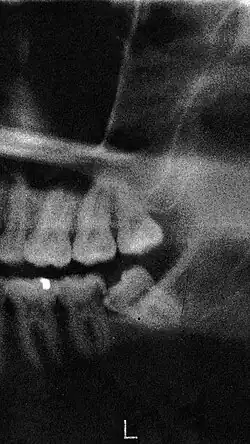

Een doorbrekende verstandskies 48 bij een 22-jarige vrouw

Wanneer een verstandskies voor problemen zorgt, kan de tandarts de verstandskies verwijderen. Wanneer hij het verwijderen van een verstandskies als moeilijk beschouwt, zal hij de patiënt vaak doorverwijzen naar een kaakchirurg. Vaak zal van tevoren een röntgenfoto van de verstandskies gemaakt moeten worden om de wortelstructuur van de verstandskies te kunnen zien. Wanneer de kaakchirurg het besluit neemt, dan wordt de kies onder plaatselijke verdoving getrokken. In enkele gevallen wordt de verstandskies in twee of drie delen verwijderd. Wanneer de patiënt angst voor dit soort behandelingen heeft, dan kan diegene kiezen om de verstandskiezen onder sedatie te laten trekken. Dit gebeurt vaak poliklinisch. Een alternatief is de verstandskiezen onder narcose laten trekken, dit vereist wel een dagbehandeling of een opname in het ziekenhuis. Deze ingreep duurt maximaal een uur.